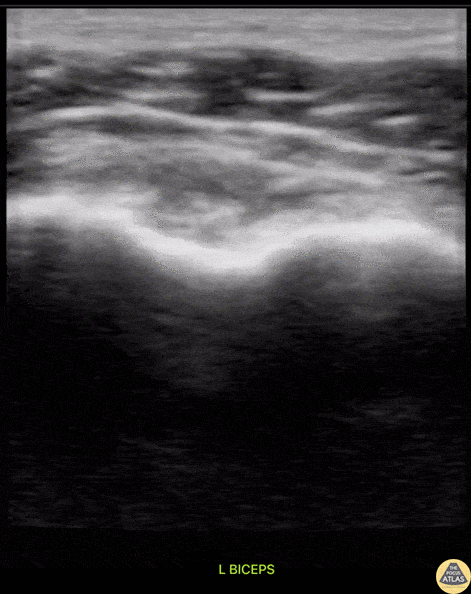

A middle aged male presented to the ED with shoulder pain after skiing crash. POCUS of the shoulder was performed, showing a subscapularis tendon tear. Here, the proximal humerus is shown in short axis, with the linear probe placed in transverse orientation at the anterior aspect of the shoulder. The biceps tendon is seen in the biceps groove, between the greater tuberosity (lateral or right of screen) and lesser tuberosity (medial or left of screen). The patient is asked to externally rotate the arm, which brings the subscapularis tendon into view, and a hypoechoic, thickened area is seen, indicating a tendon tear. Dr. Matthew Riscinti Denver Health Medical Center